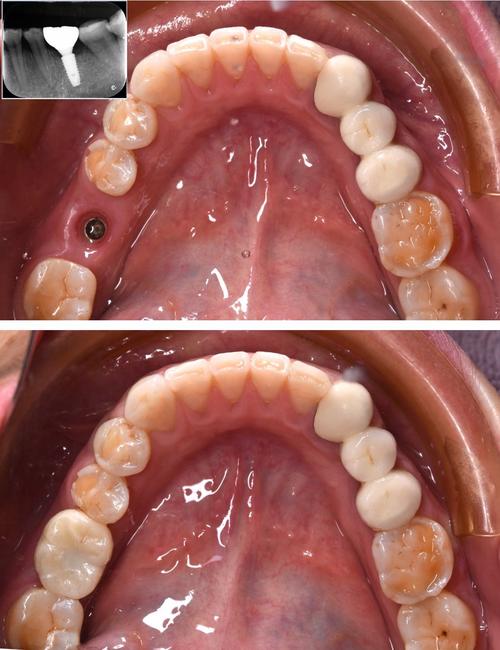

(图片来源网络,侵删)- 高水平医院众多: 广州拥有众多实力雄厚的大型三甲医院(如中山大学附属口腔医院、南方医科大学南方医院、广东省口腔医院等),其口腔科/种植中心拥有顶尖的专家团队、先进的设备(如CBCT、口内扫描仪、3D打印导板等)和丰富的临床经验,尤其擅长处理复杂病例。

- 技术普及度高: 即刻种植、微创种植、数字化导板种植、All-on-4/6等先进技术在广州的大型医院和知名私立诊所都已广泛应用。